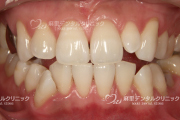

ホワイトニングや審美歯科治療後の素敵な笑顔です。

ただし、歯ぐきの写真などを気持ち悪く感じる方は、あまり見ないでくださいね。